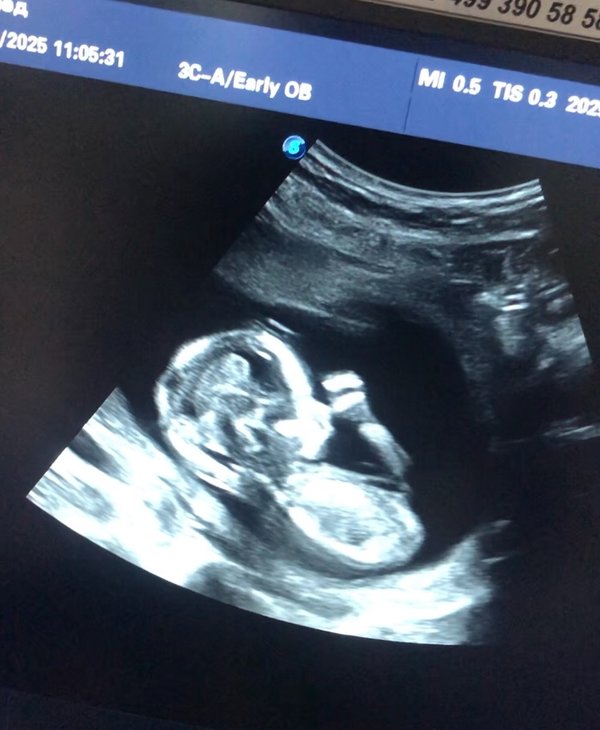

УЗИ диагностика. ‼️По записи Без очереди ⏰Ежедневно с 10:00 до 17:00 ️Перерыв с 13:00 до 14:30 ️Суббота с 10:00 до 15:00 ‼️Воскресенье ВЫХОДНОй --- Бородулина Наталья (Врач УЗИ, Косметология) (27.10.2025): Магия Первой Встречи: #УЗИ до 11 недель и Тайная Жизнь Внутри Вас 1. Он уже не «точка»‼️ У него уже есть головка, тельце и даже видны зачатки ручек и ножек, которые сейчас больше похожи на плавнички. 2. Он не просто лежит — он ДВИГАЕТСЯ‼️ Да-да, вы не ослышались! Уже с 7—8 недель малыш начинает совершать свои первые, еще хаотичные, но такие… — Читать дальше

трогательные движения. Он может взмахивать ручками, подпрыгивать, отталкиваться от стенок матки. ️ Возьмите с собой самого близкого человека. Разделите эти незабываемые эмоции с партнером. Это #УЗИ — ваш первый семейный портрет. Тот самый снимок, который вы унесете с собой, будет самым ценным кадром. На нем — не просто пятнышко. На нем — вся ️вселенная, уместившаяся в несколько сантиметров.

Бородулина Наталья (Врач УЗИ, Косметология) (27.03.2025): #УЗИ беременных: Ваш путь к чуду жизни! Каждый момент ожидания — это удивительное приключение‼️ УЗИ — не только возможность увидеть своего будущего малыша, но и важный шаг в заботе о здоровье вас и вашего ребенка. Что дает УЗИ? — Определение срока #беременности — Мониторинг развития плода — Выявление возможных аномалий — Определение пола ребенка (в некоторых случаях) Преимущества УЗИ: — Безопасно и безболезненно — Позволяет вам увидеть вашего малыша на экране — Возможность записа… — Читать дальше

ть видео или #фото для воспоминаний ️ Не упустите шанс‼️ Запишитесь на УЗИ и подарите себе и вашим близким уникальные эмоции!